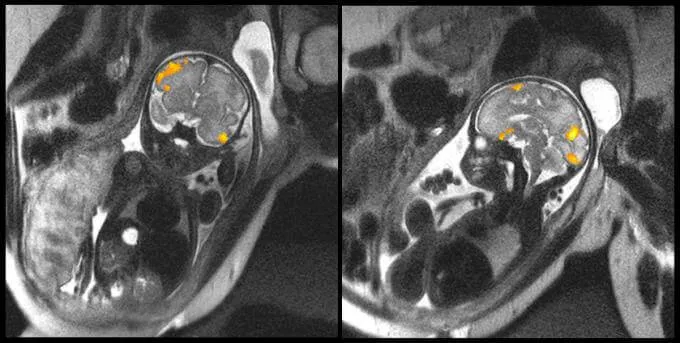

A felső képen egy magzat MRI-jét láthatjuk 20 hetesen, egy másikat 40 hetesen.

A teszteket végző tudósok egyik kiemelt célja az volt elemezni A kapott adatok eddig ismeretlen szempontokat tártak fel a koraszülöttekkel kapcsolatban.

Az első tanulmány adatait a folyóiratban tették közzé Tudományos Jelentések Az elemzés kiegészítéseként az új mágneses rezonancia képalkotással 36 terhes nőt vizsgáltak meg a huszadik héttől a harminchatodik hétig. Felük nagy kockázatú terhesség volt, a babák pedig koraszülöttek.

- Ezt ki lehetett deríteni azok a magzatok, amelyek az idejük előtt születtek volna, nagyon gyenge kapcsolattal rendelkeztek alatt más magzatokhoz képest

- Eddig azt hitték, hogy a koraszülött gyermekeknél észlelt alacsony agyi konnektivitás főként a traumás szülésnek vagy a sokak hipoxiának köszönhető.

Ez az új bizonyíték azonban egyértelműen ezt igazolta az alacsony neuronaktivitás már az anyai méhen belül is megmutatkozik és hogy a neuronok közötti rossz kapcsolat nagyon szembetűnő Brocca területén, vagyis a nyelvi feldolgozással kapcsolatos területen.